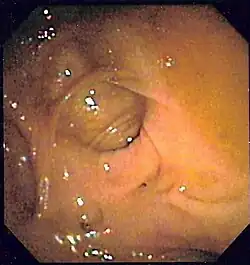

Wrzód żołądka, białe dno owrzodzenia

U chorych z podejrzeniem krwawienia z górnego odcinka przewodu pokarmowego gastroskopia jest postępowaniem z wyboru, która ma znaczenie diagnostyczne i lecznicze[1]. Badanie ma na celu potwierdzenie rozpoznania krwawienia z górnego odcinka przewodu pokarmowego, określenie lokalizacji i źródła krwawienia, kwalifikację oraz wykonanie zabiegów endoskopowych zatrzymujących krwawienie[117]. Szacuje się, że czułość wykrywania źródła krwawienia z górnego odcinka przewodu pokarmowego wynosi 92–98%[1].